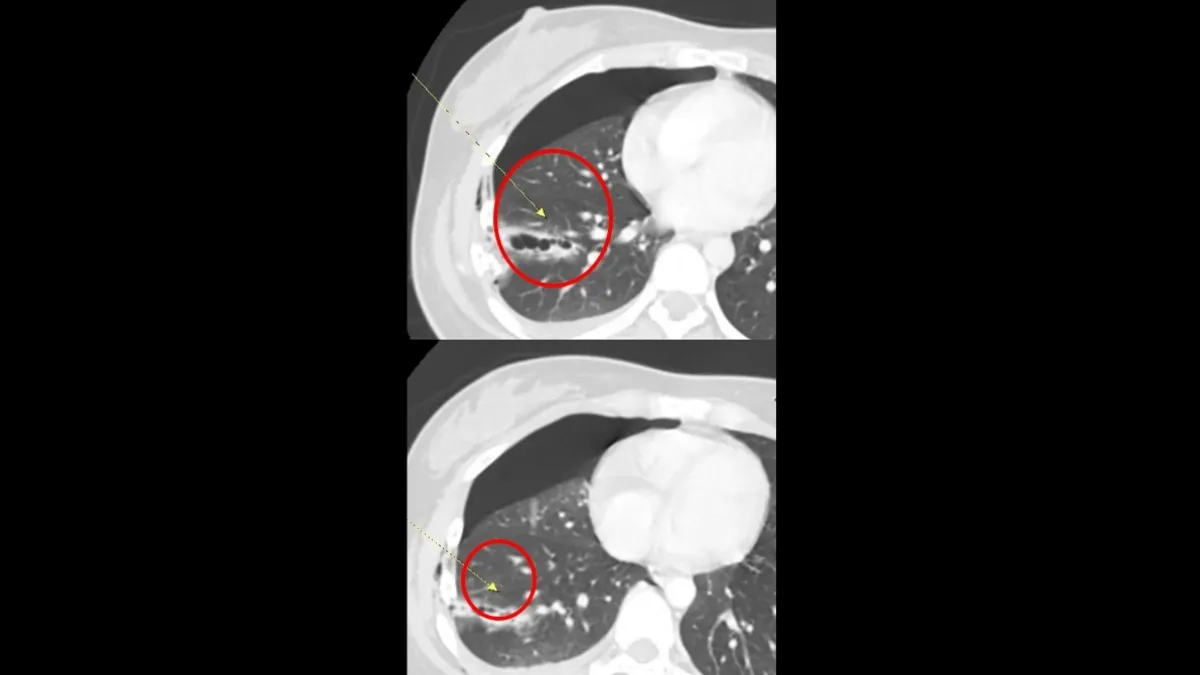

澄清醫院胸腔外科主任杜承哲指出,胸腔損傷最怕的就是「溫水煮青蛙」,外表看似無大礙,內部卻在持續出血。這名病患經電腦斷層掃描確認,第5至7節肋骨骨折,其中有兩節直接插入肺組織,導致肺臟破裂。

隨著胸腔內積血持續增加,嚴重壓迫肺部擴張,若單純引流恐無法止血。醫療團隊評估,若不立即處理,患者隨時可能因呼吸衰竭或休克而危及生命,決定立即進行手術。